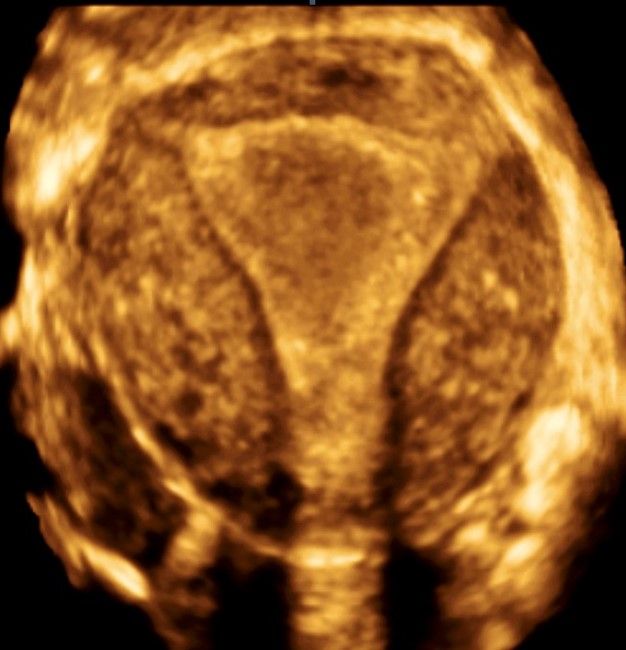

Современные экспертные УЗИ сканеры дают возможность проводить исследования всех органов в 3D. Это позволяет, используя полученный массив данных, получать диагностические сечения в любой плоскости, недоступной для обычного 2D УЗИ. Наиболее интересной является фронтальная. Например, визуализация полости матки. Диагностическая возможность выявления пороков развития превосходит все другие методы (рентгеновские и МРТ). Метод также позволяет уточнить положение ВМК (спирали) в полости матки, расположение миоматозных узлов, расположение плодного яйца на малых сроках, полипов. Сегодня современное экспертное ультразвуковое исследование невозможно без использования 3D УЗИ.